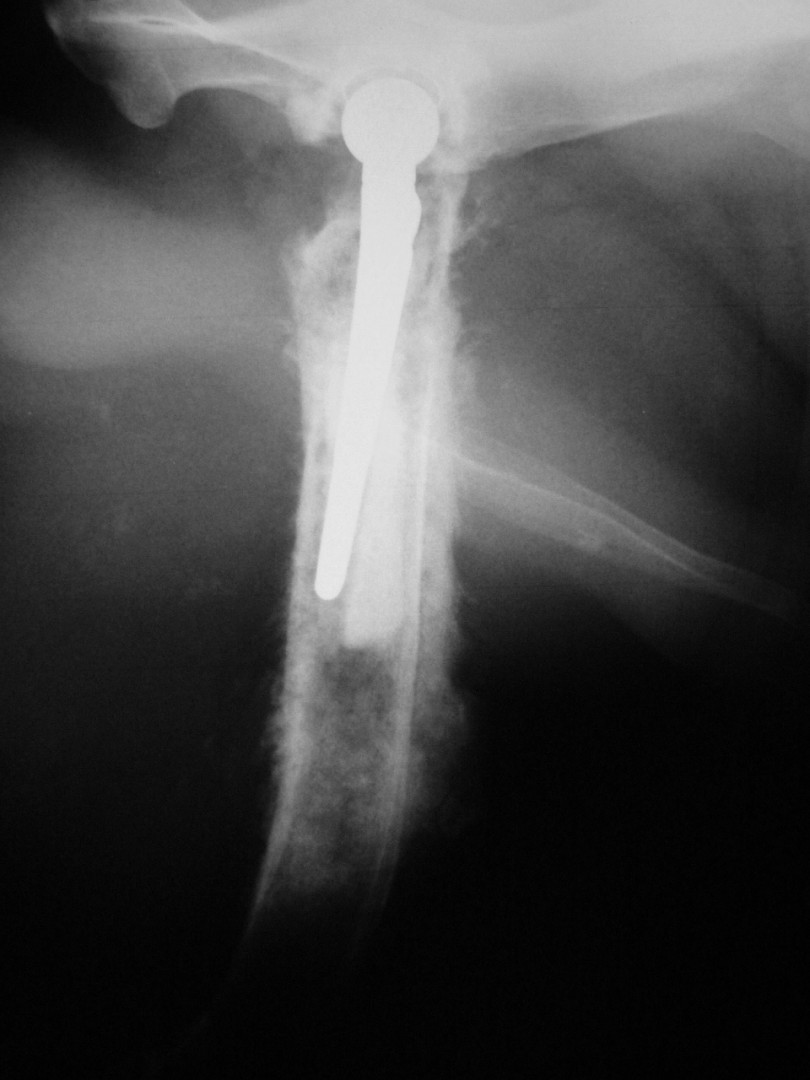

Bár a csípőízület megbetegedéseiről – mint a leggyakrabban tárgyalt ortopédiai megbetegedésről- első körben nem szerettem volna szólni, mégis megteszem, mert 2010. májusában egy hosszabb egyeztetést és szervezést követően beültettük az első teljes csípőízületi protézist…

A szervezés két részből állt: egyrészt felkerestük azt a magyarországi gyártót, aki a hazai anyagi lehetőségeket is figyelembe véve a szakmai szempontból is optimális rendszert le tudja gyártani, másrészt rábeszéltem Kendik Zsolt kollégámat, aki a hazai csípőízületi protézis beültetésének úttörője, hogy legyen segítségemre a műtét technikájának elsajátításában.

A tényleges műtét előtt temérdek teendő akad. A kutya teljes belgyógyászati kivizsgálása, egyéb ortopédiai és/vagy neurológiai betegségek kiszűrése, a tulajdonosokkal folytatott többszöri megbeszélés, a kockázatok mérlegelése és ezek részletes ismertetése jelentős energiát emészt fel. De ezek nélkül a beteg állat tulajdonosa nem tud reális döntést hozni: vállalható-e a műtét vagy sem?A műtéti időpont egyeztetése sem egyszerű: az operáció során 4 ember összehangolt munkájára, tökéletes aneszteziológiára és a műtétet követően az asszisztensek gondos munkájára van szükség a teljes gyógyuláshoz. Ez szintén jelentős szervezést igényel. A műtétet követő 10 napos kórházi ápolás és az ez utáni 3 hónapon át tartó szigorú mozgáskorlátozás betartása és betartatása a gyógyulás elengedhetetlen feltétele. Egy fiatal, ereje teljében lévő, energikus kutyánál ez néha nehezebb feladat, mint maga az operáció.

Az első műtét remekül sikerült és Connor, a skót juhász kutya megkapta a bal oldali új csípőízületét. A 7 napi kórházi tartás is problémamentesen zajlott és a varratszedés idejére a műtött végtag terhelése gyakorlatilag hibátlan volt. Az 1 hónapos és a 3 hónapos kontroll RTG vizsgálatokon sem jelentkezett szövődményre utaló jel, az 1 éves postoperatív időszakban már csak az látszott, hogy a műtött lábát jobban terheli, mint a nem operált végtagot. Így 2011. júniusában – immár sokadik csípőízületi protézis műtétként- a jobb oldali csípőízületét is megoperáltuk. Connor gyakorlatilag azóta teljes életet él és vidáman játszik társaival, még birkákat is terel…A majd két éves, a protetizálás során szerzett tapasztalatok azonban nálunk is hozzák a szakirodalomban leírt szövődményi lehetőségeket és arányokat. Leggyakrabban a beültetett protézis ficamával találkoztunk, de akadt sajnos kilökődési reakció is. Ezen problémák – az előzetes tájékoztatás ellenére is- mindig váratlanul érik a tulajdonost és az állatorvost egyaránt. Megoldásuk szinte kizárólag műtéti, ami újabb kockázatot, újabb fizikai és anyagi áldozatot jelent.